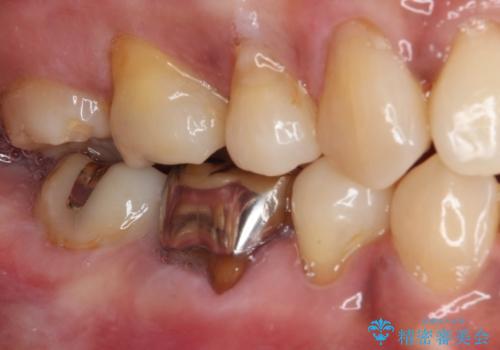

- 矯正治療後に、下顎奥歯の銀歯をすべてゴールドにすることを希望された患者様です。

セラミッククラウンやセラミックインレーによる補綴治療も提案しましたが、お友達にゴールドを自慢したいとのことで、ゴールドクラウンとゴールドインレーにて処置することとしました。